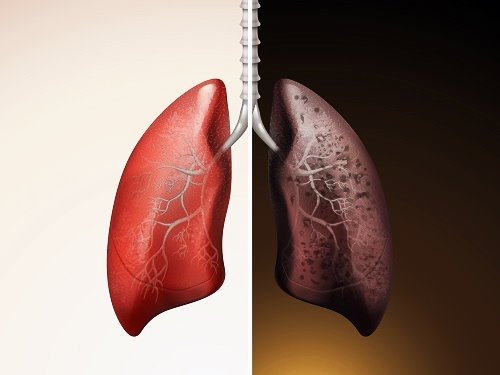

폐암 초기증상은 호흡관란, 지속적인 기침 및 가래, 흉통 등이 있으며, 조기발견과 정확한 진단이 중요합니다. 아래에서는 폐암 초기증상에 대해 자세히 알아보고 조기 발견할 수 있도록 도움이 되었으면 합니다.

폐암 초기증상

폐암 예방법

흡연은 폐암의 가장 큰 원인 중 하나입니다. 담배를 피우지 않거나 금연하는 것이 폐암 예방에 가장 효과적입니다. 만약 흡연 중이라면 의사나 금연 전문가의 도움을 받아 금연 계획을 수립하는 것이 좋습니다.